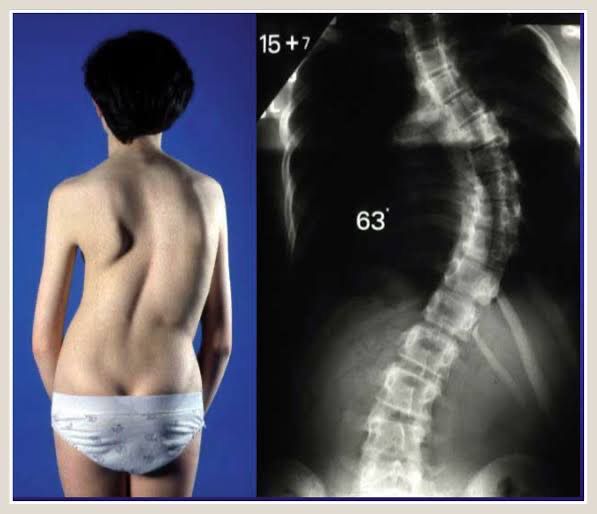

Scoliosis is a spinal deformity where the spine is curved sideways. The curve is defined as “S” or “C” shaped deformity. Signs and symptoms are visible deformity, pain, cardiorespiratory problems and problems with mobility. Main causes are: 1. Idiopathic: Due to unknown causes. 2. Congenital: Present at birth. 3. Degenerative: Result of degeneration of disc in uneven fashion. 4. Neuromuscular: Involves neuromuscular diseases. 5. Thoracogenic: Due to radiation exposure in childhood 6. Syndromic: Associated with underlying syndrome. Treatment modalities are observation, bracing, surgery, pain medications and posture checking. Picture credits: https://www.orthopaedicsandtraumajournal.co.uk/article/S1877-1327%2817%2930100-8/fulltext